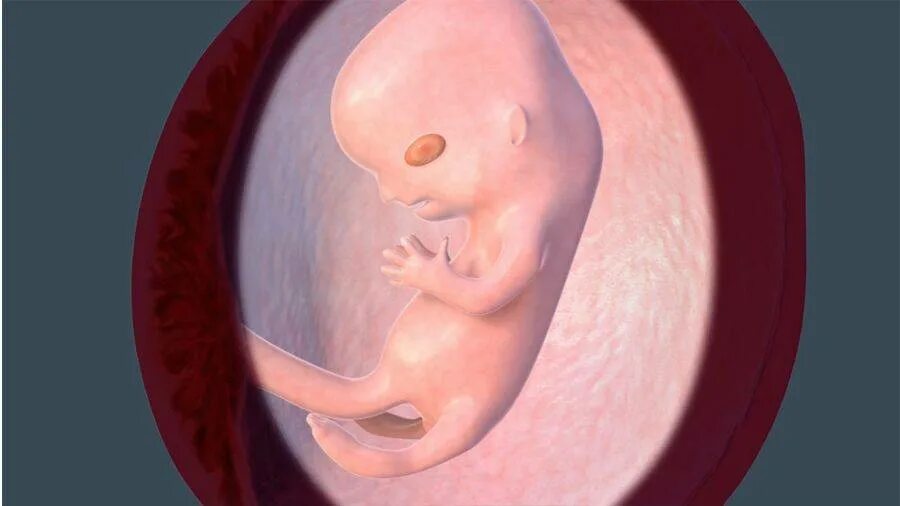

11 недель ощущения